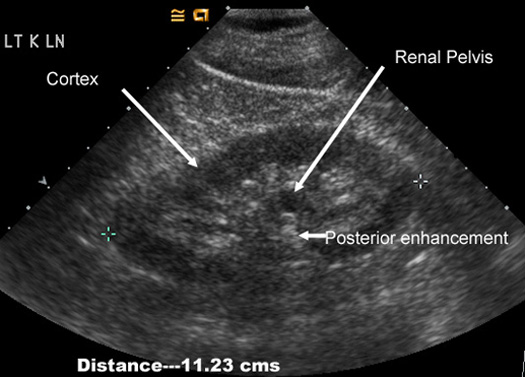

Normal kidney in US:

Measures 9-11 cms

Has the same extent of echoes as liver

Cortex measures about 2.5 cms

Central echoes are from fat surrounding renal pelvis.

Renal pelvis is filled with urine and is echo free. Note the posterior enhancement behind renal pelvis.